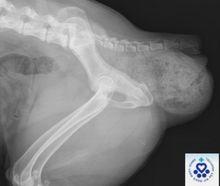

犬會陰疝5.尿道膀胱X線片可見顯示尿道和膀胱在疝中。